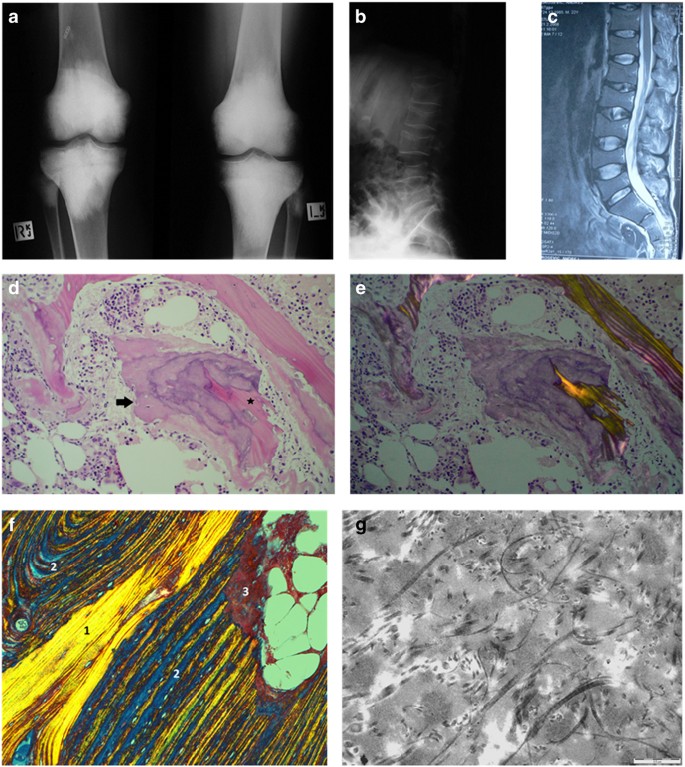

Plain radiographs showed a marked increase in bone density in a bilateral and symmetrical manner affecting the metaphyseal regions of the long bones including the distal femora (Figure 1a), proximal and distal tibiae, greater trochanteric region of the proximal femora, distal humeri, proximal radius, and ulnae. In the spine, marked osteopenia was evident with central collapse of the endplates that had a concave appearance (Figure 1b and c). A nuclear bone scan showed increased uptake in the bones around the knees and ankle joints in a symmetrical pattern at the sites of increased bone density. The bone mineral density of the lumbar spine and femoral neck was measured by dual X-ray absorptiometry (DXA) (Hologic Explorer). The spinal bone mineral density (BMD L1–4) was 0.532 g·cm−2 (T score −5.1) and the left femoral neck BMD was 0.631 g·cm−2 (T score −2.3). He received alendronate 70 mg per week, for 3–4 weeks.

Radiograph of the knees (a) shows marked bilateral symmetrical homogeneous sclerosis involving the epiphyses and metaphyses, involving all bones related to the joint. Radiograph and T2-weighted MR image (b and c) shows central collapse of the vertebral end plates associated with osteoporosis. In the iliac crest bone marrow trephine, variably sized bone trabelculae are noted with intervening haemopoeitic marrow (d). In thicker trabeculae, wide irregular osteoid seams with calcification are noted (arrowed). Normal slender trabeculae of lamellar bone are presented focally. The intervening immature osteoid has irregular zones of calcification stained in blue. Centrally, a residual spicule of more dense pink normal lamellar bone (star) is bordered by zones of immature pink osteoid with irregular poorly defined zones of calcification, the calcification predominating where the osteoid abuts the bone trabeculum and diminished at the perimeter (arrowed). On polarization microscopy of the same area (e), the original host lamellar bone with generous quantities of collagen birefringence is minimal. In the femur biopsy, a Masson trichrome stain examined under polarized light (f) shows original host bone with cohesive and generous collagen content (zone 1). This is bordered by a thick area of coarse lamellar bone in which the blue areas represent the separation between the collagen bundles (zone 2). At the top right, a small area of immature osteoid (zone 3) is evident that is largely devoid of collagen. Electron microscopic findings in the femur biopsy (g) show abnormally curved and randomly oriented fibres of variable diameter that are easily identifiable within the matrix.

A bone marrow biopsy and aspirate from the right posterior superior iliac spine carried out on the 10 April 2008 to further evaluate the significance of the circulating IgG kappa monoclonal protein showed that the marrow was normocellular with all cell lines present to maturity. There was a slight increase in megakaryocyte numbers. Very mild plasmacytosis was seen (3%) and kappa IgG was predominant. Chromosomal analysis was normal. A diagnosis of monoclonal gammopathy of uncertain significance was made. The bone biopsy obtained by trephine comprised cancelous bone and hemopoietic marrow. In some regions, sparse very slender trabeculae were noted and elsewhere the trabeculae had a thicker appearance. In the latter, widened osteoid seams were prevalent in which irregular calcification was noted giving the impression of prominent and wide cement lines. These were bordered by plump osteoblasts and admixed osteoclasts were present. On polarization microscopy, there was a paucity of collagen fibers within the thickened osteoid seams. In some of the thickened seams, residual spicules of original normal lamellar bone were identifiable (Figure 1d and e).Features suggesting microtrabecular fracture were also identified.

A subsequent open distal femoral biopsy to include cortex and medulla within the metaphyseal sclerotic area was performed on 14 June 2008 to further characterize the bony abnormality and to obtain bone for cell culture. At surgery the surgeon documented very hard bone. The biopsy comprised periosteum, cortex, and medulla measuring 30×10×4 mm and was suitable for morphometric, microbiologic, and electron microscopic examination. Cultures for aerobic and anaerobic bacteria were negative. Fungal elements were not seen. A stain for spirochetes was negative. Several fragments were placed in transport medium for cell culture. Despite the hardness of the bone documented at surgery, decalcification of the specimen was brisk, occurring within 4 h, suggesting ease of release of the mineral component. The component bony trabeculae within the medullary cavity were thick with a varying lamellar architecture. They were comprised of central zones of mature lamellar bone in which densely packed collagen with a smooth homogeneous polarization pattern was identifiable. This was bordered by broad zones of thick coarse lamellar bone in which the collagen fibers, although arranged in a lamellar pattern were distinctly separate one from one another. In some regions, these were in turn bordered by a third wave of ossification in which even less collagen content was demonstrable on polarization microscopy. These findings were confirmed with Masson Trichrome (Figure 1f) and reticulin staining. Scattered foci of osteoclast resorption were noted and in some regions resorption pits were filled with immature osteoid with diminished collagen content. Osteoblasts were inconspicuous throughout in contrast to the plump osteoblasts seen in the bone marrow biopsy.

Electron microscopic examination showed seams of osteoid at the surface of the lamellar bone in which very sparse collagen fibrils of varying diameters were present. The collagen fibers were randomly oriented and many were small, irregularly shaped, and curved. Scattered irregular mineralization foci were present and mineral lay within a pale amorphous matrix (Figure 1g).This contrasts with normal bone where there is an orderly parallel orientation of collagen which is tightly arranged. The constellation of changes reflect those of diminishing collagen content within the osteoid of each modeling cycle accompanied by abnormal collagen fibers on electron microscopy. These features are consistent with those documented in fibrogenesis imperfecta ossium.1–4 Subsequently, from 2 months after the femoral bone biopsy, the patient received infusions of zolendronate, 4 mg, every 6 months. The spinal BMD showed a step-wise increase from 0.532 to 1.111 g·cm−2 (T score 0.2) over 7 years to 2015. In the same time interval, the left femoral neck BMD increased to 0.986 g·cm−2 (T score 0.4). In September 2009, the patient developed a fever and endocarditis due to salmonella. An aortic valve replacement was performed soon after.